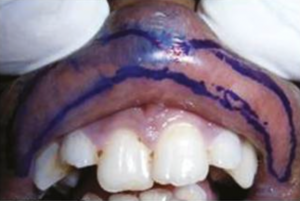

また、患者さんの特定の唇の形状や、より繊細な美的要求に応えるために、「蟹爪テクニック」と呼ばれる、切開の形を工夫する術式も選択肢の一つとなります。このテクニックは、唇の厚みを効果的に減らしつつ、個々の方の顔立ちに合わせた、より自然で個性的な唇の美的輪郭を形成するのに役立つとされています。いずれの術式も、安全で比較的単純な手技であると評価されており、適切な診断と治療基準が満たされれば、患者さんの満足度が高い結果が期待できるものです。当院では、患者さんの唇の状態とご希望を詳細にお伺いし、最適な術式をご提案いたします。

crab claw design